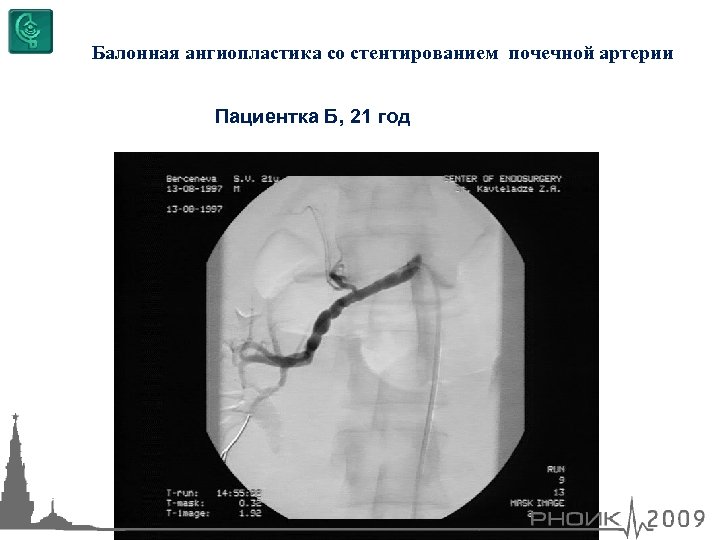

Баллонная ангиопластика со стентированием почечной артерии Пациентка Б, 21 год

Баллонная ангиопластика со стентированием почечной артерии Пациентка Б, 21 год

Балонная ангиопластика со стентированием почечной артерии Пациентка Б, 21 год

Балонная ангиопластика со стентированием почечной артерии Пациентка Б, 21 год